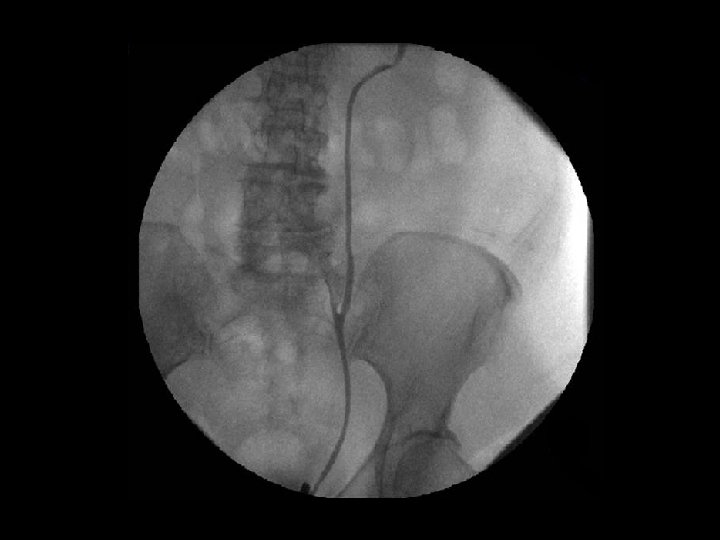

Vyšetření • • endoskopie urethrocystografie cystoskopie vyšetření mikce

Nemoci močových cest • • nefrolitiáza hydronefróza ruptura pánvičky vezikoureterální reflux uroinfekce urolitiáza + renální kolika divertikly nádory (papilomy, papilokarcinomy)

Léčebné zásahy • LERV (litotripse extrakorporální rázovou vlnou) = ESWL (extracorporeal shock wave lithotripsy) • URS (ureteroskopická lithotripse) • sondáž močovodu (endoskopické zavedení stentu)